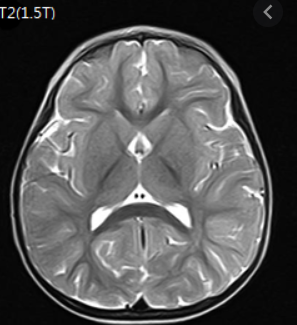

하지만 재정악화 및 무분별한 MRI 시행으로 또 제도가 바꼈습니다. 2020년 4월 1일에 개선안이 나왔는데요.

신경학적 검사상 이상 증상 또는 뇌혈관 질환이 강력하게 의심되는 경우에만 건강보험이 적용되는걸로 바꼈습니다.

그리고 뇌질환이 의심되는 두통, 어지로움으로 MRI 검사를 받았다면 본임부담이 80%로 바꼇습니다. 그렇기 때문에 의사의 판단하에 따라 금액이 많이 차이가 나게 되었습니다.

보통 MRI 보험적용은 의사의 진료하에 따라 확인이 가능하게됩니다. 이상소견이 없다면 비급여로 처리되기 때문에 금액이 최소 50~100만원 정도 금액이 청구됩니다.